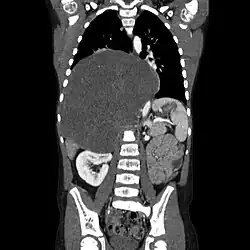

CT scan of a large ganglioneuroma within the chest cavity